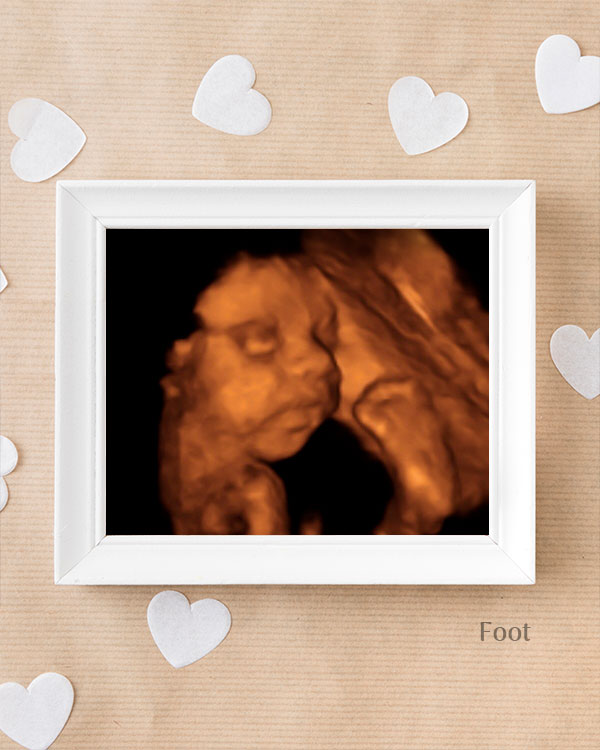

3D / 4D Baby Scan

Mediserv Diagnostics pioneered 4D scanning in the Malabar region. These advanced scans provide realistic images of the baby, allowing detailed evaluation of fetal structures and movements while creating a meaningful bonding experience for parents.